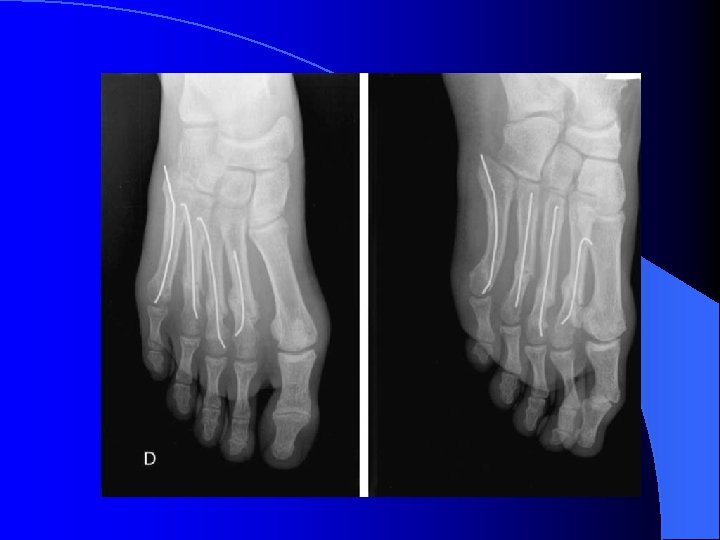

Fractures diaphysaires, F cols métatarsiens l Choc direct écrasement, pied barreaux échelle l Restituer arche métatarsienne l Appui le plus vite possible pour remodelage l Si grand déplacement réduction ostéosynthèse, brochage

Fractures et luxations des orteils l Très fréquentes l Choc direct l Réduction de la luxation souvent facile l Immobilisation par syndactylie l Fractures P 1 gros orteil déplacées : réduction ostéosynthèse